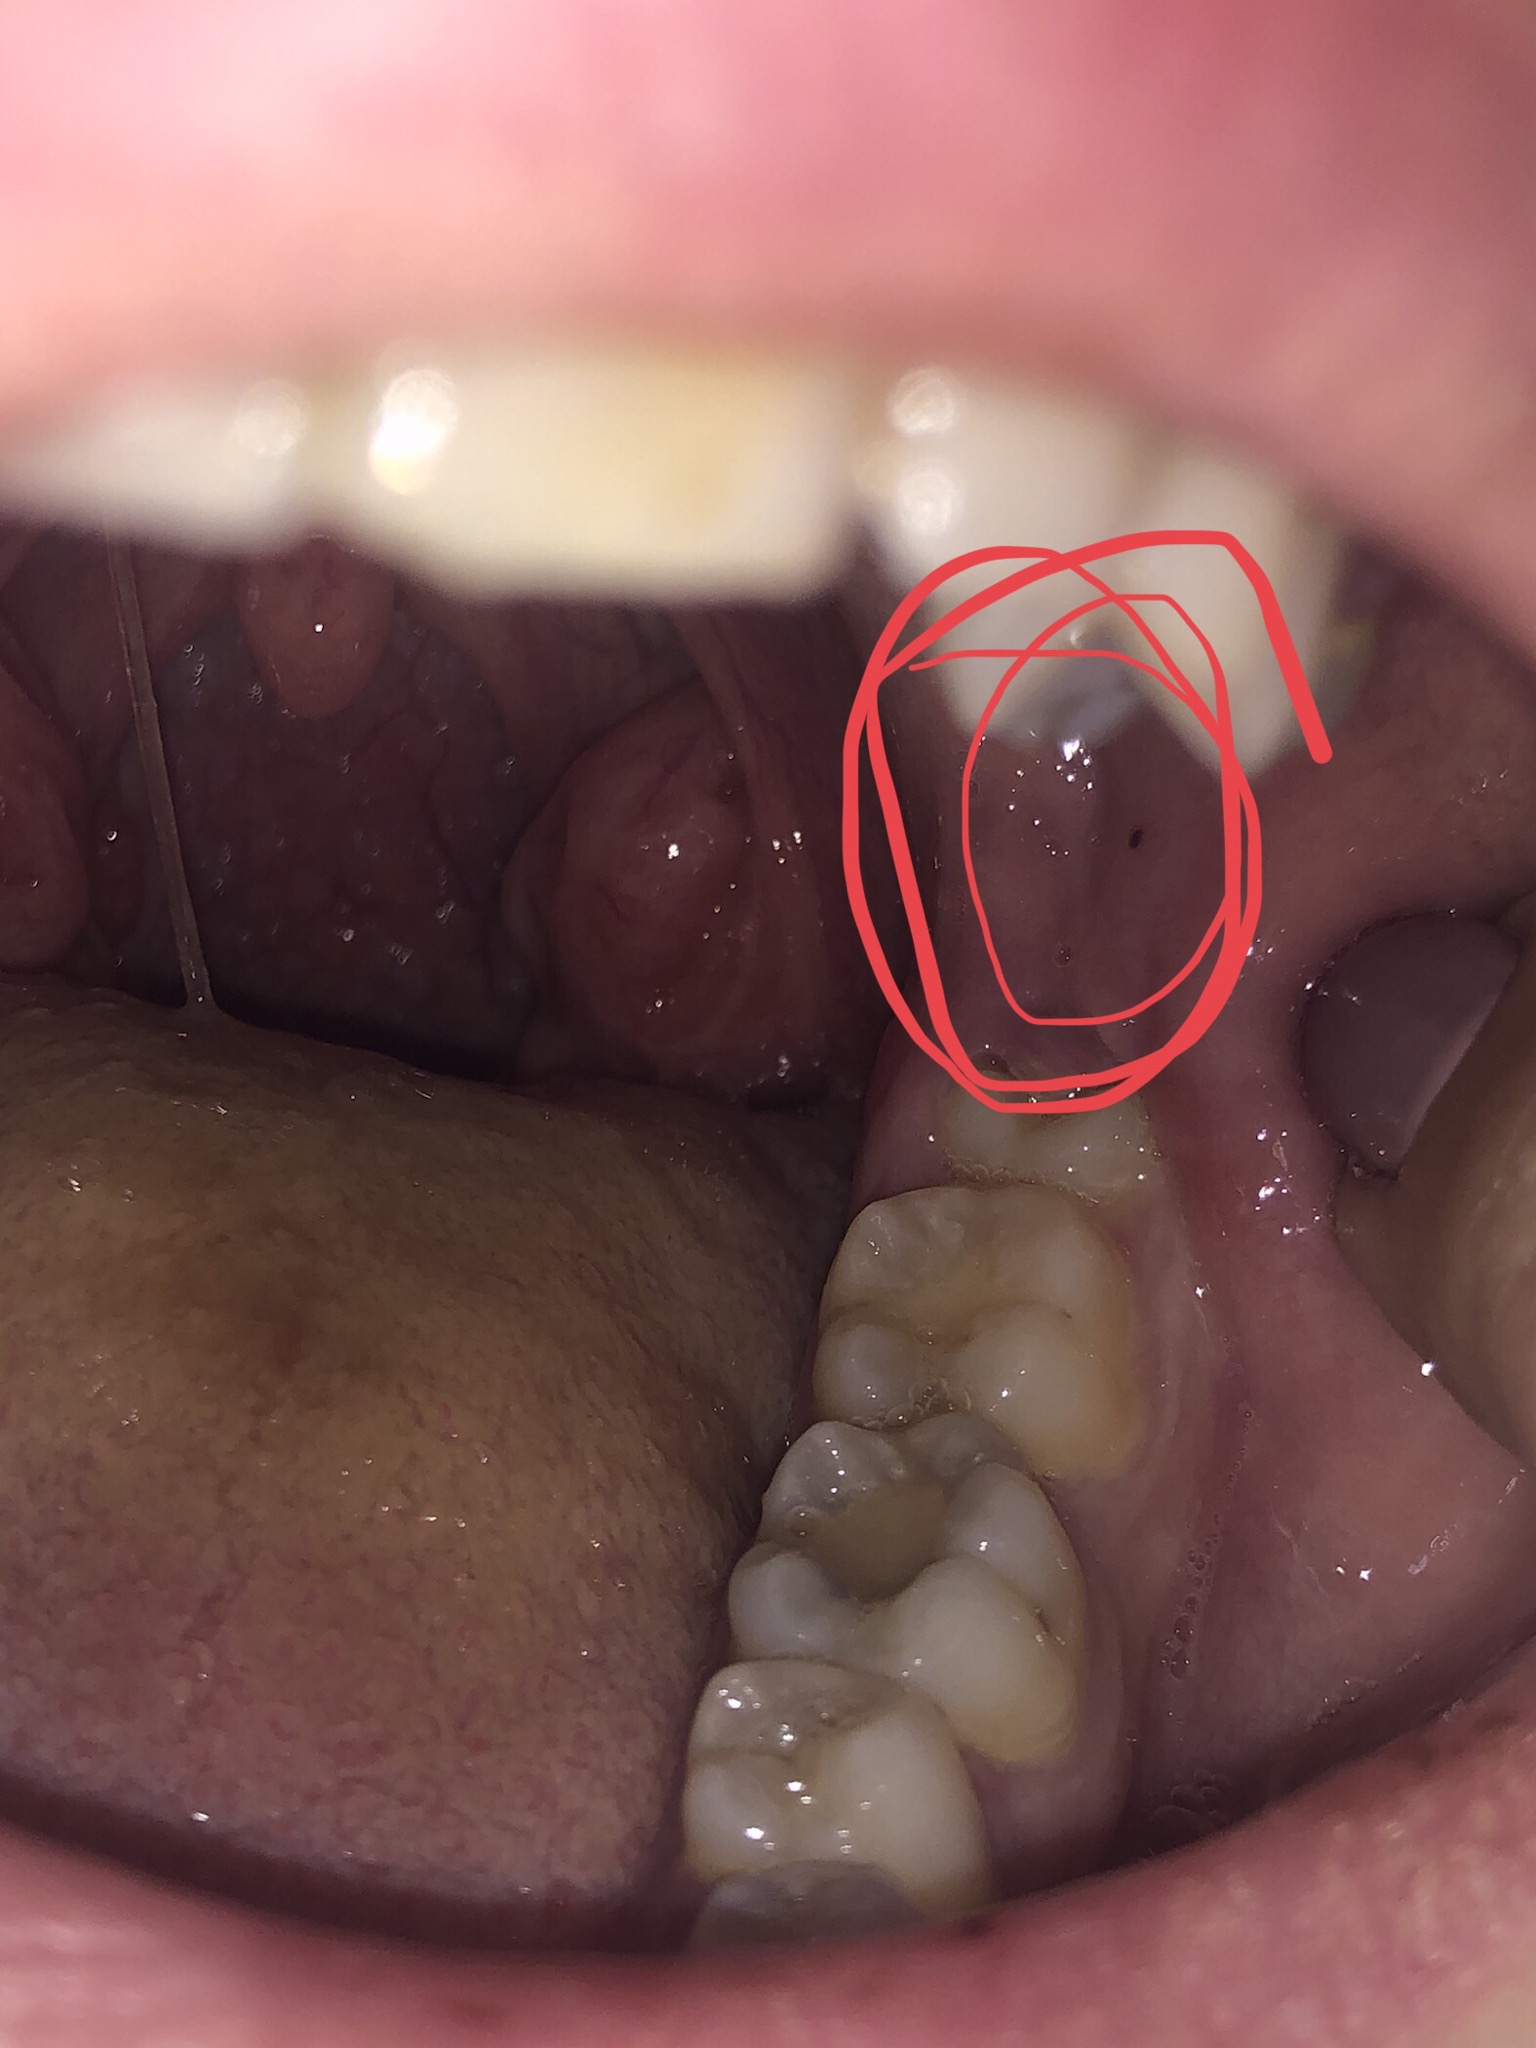

От 3 дни имам проблем с езика - силна пареща болка (наподобяваща болката при изгаряне с гореща храна/ напитка), налепи, гнойни образования (като пъпчици) и малки кървави "точици" (все едно е езикът е прободен с игла). Вчера премахнах налепа с помощта на четката за зъби, но отново се появи и дискомфортът е много голям, особено при хранене.

Ще се консултирам и със стоматолога си, и с личния си лекар, но дотогава не знам какво да правя и съм доста притеснен... На какво може да се дължи този проблем? Прикачвам снимка, за да придобиете визуална представа.

- снимка.PNG (517.37 KiB) Прегледано 1923 пъти